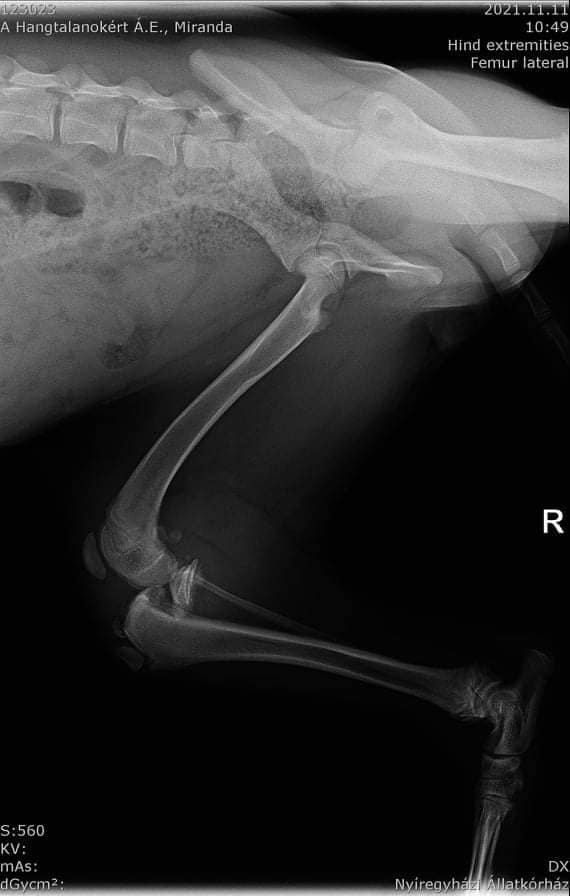

Vergangene Woche wurde die Junghündin Miranda verletzt auf der Straße gefunden. Ein Besuch in der Tierklinik ergab ein gebrochenes Hinterbein, welches operiert werden musste. Als zweiter Sorgenfall wurde Hündin Odri der Tierklinik vorgestellt, weil sie auffällig humpelte. Die Untersuchung ergab, dass ein alter Bruch Odri Schmerzen bereitet. Dieser wurde vermutlich durch einen Autounfall verursacht. Auch Odris Hinterlauf wurde operativ gerichtet. Beide Hündinnen haben die Eingriffe gut überstanden und genesen. Die Operationen haben ein großes Loch in die Tierheimkasse gerissen. Kosten iHv 930€ entstanden. Das Tierheim benötigt daher dringend finanzielle Unterstützung.